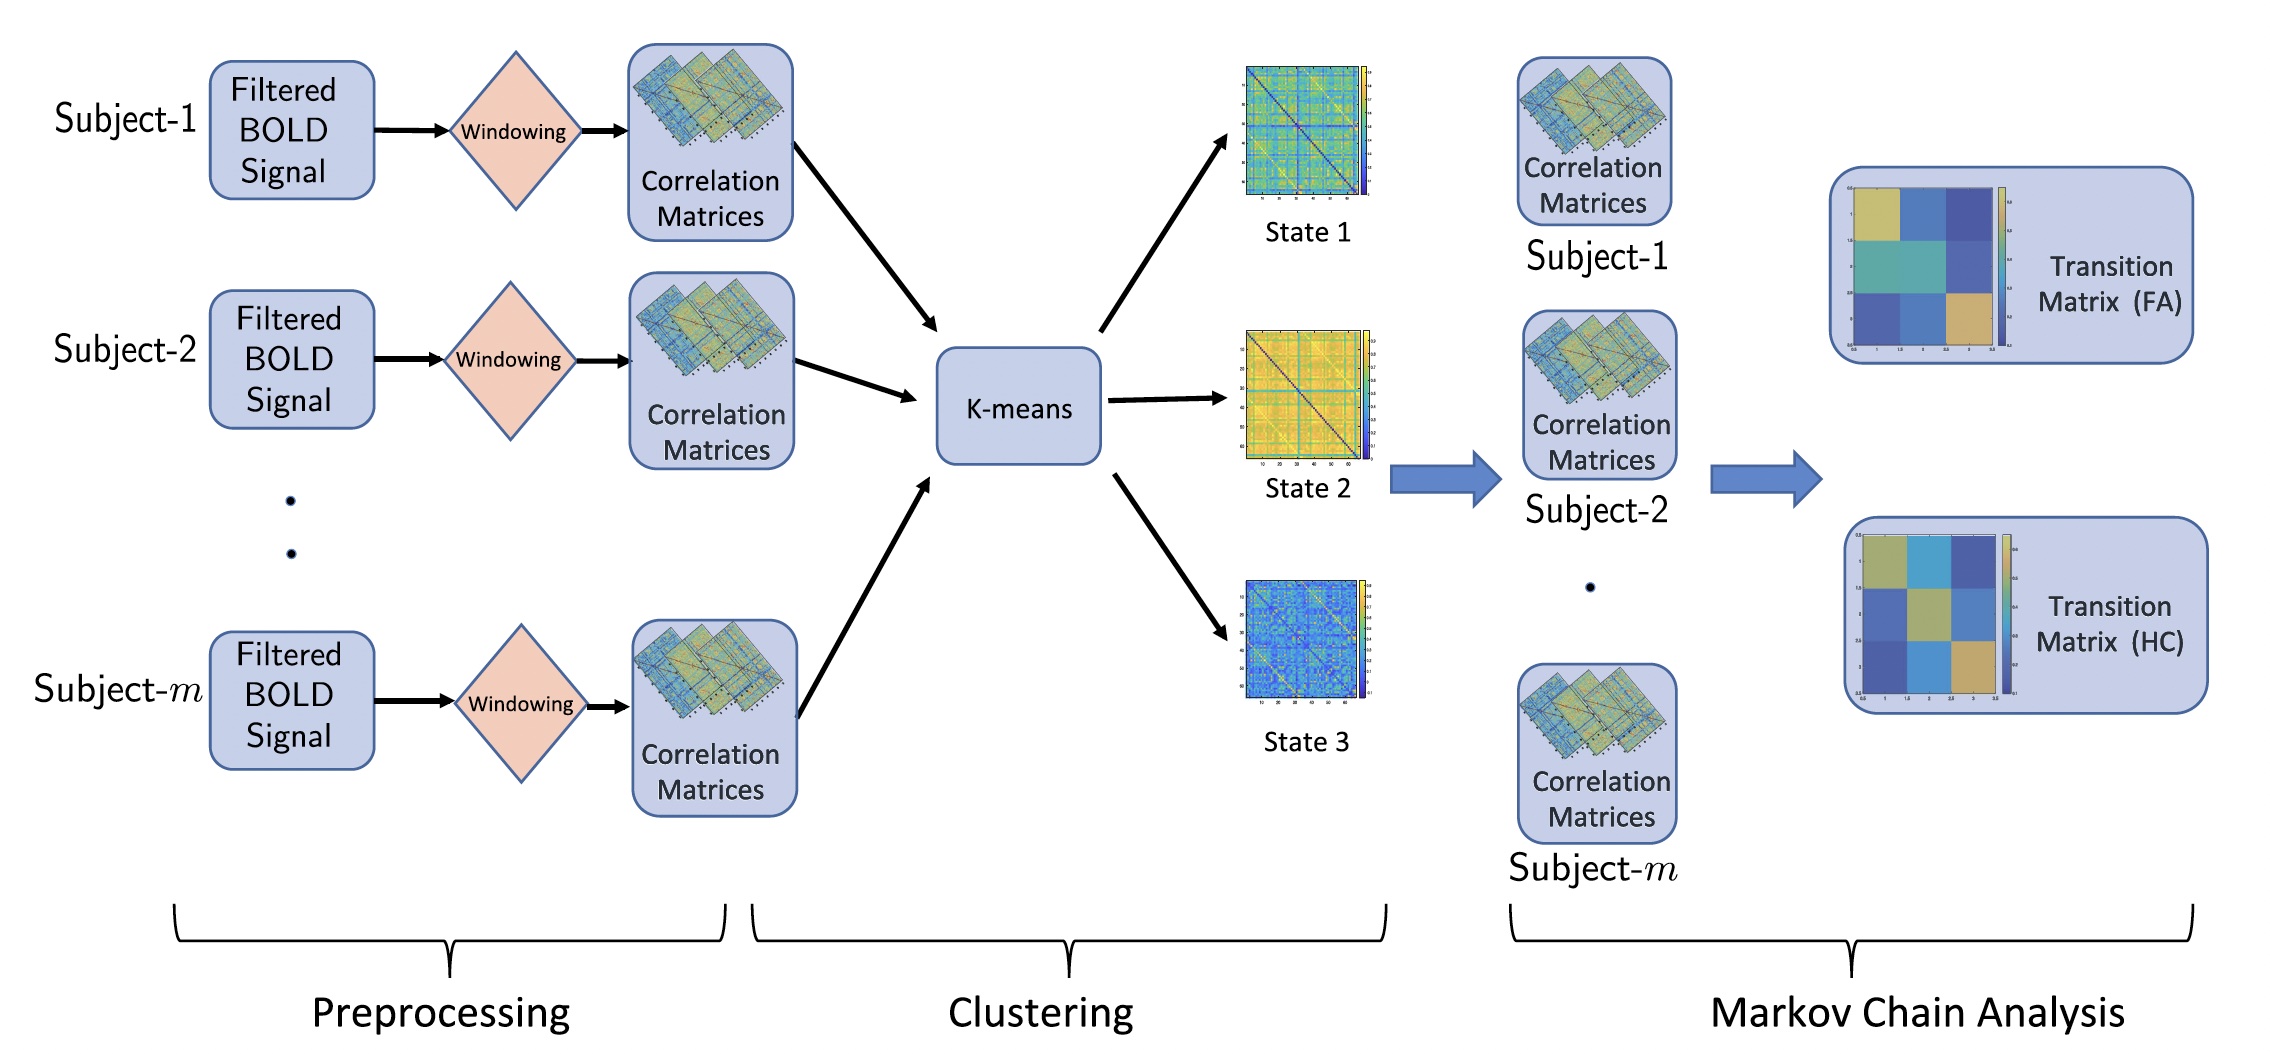

Data engineering, analysis of multimodal dataset, and multiscale modeling of neurostimulation in obsessive-compulsive disorders.